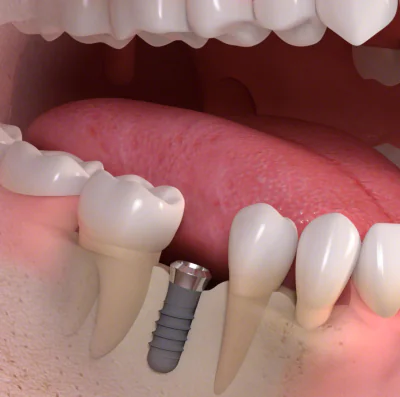

インプラント治療は、歯を失った箇所に人工の歯根(インプラント)を埋め込み、歯を補う治療法です。従来の治療法であるブリッジや入れ歯とは異なり、インプラントを顎の骨に埋め込むことで、優れた安定性を実現します。

インプラント治療は、歯を失った箇所に人工の歯根(インプラント)を埋め込み、歯を補う治療法です。従来の治療法であるブリッジや入れ歯とは異なり、インプラントを顎の骨に埋め込むことで、優れた安定性を実現します。

インプラント治療では、まず歯科医師が顎の骨の状態を評価し、適切なインプラントの種類とサイズを選定します。そして、インプラントを顎の骨に埋め込み、骨とインプラントが結合してから人工の歯冠を取り付けることで、自然な見た目と噛む機能を回復させます。

それに対して、インプラント治療では、健康な歯を利用せずに人工の歯根を埋め込み、人工の歯冠を固定します。これにより、健康な歯を保持しながら咀嚼力を回復させることができます。